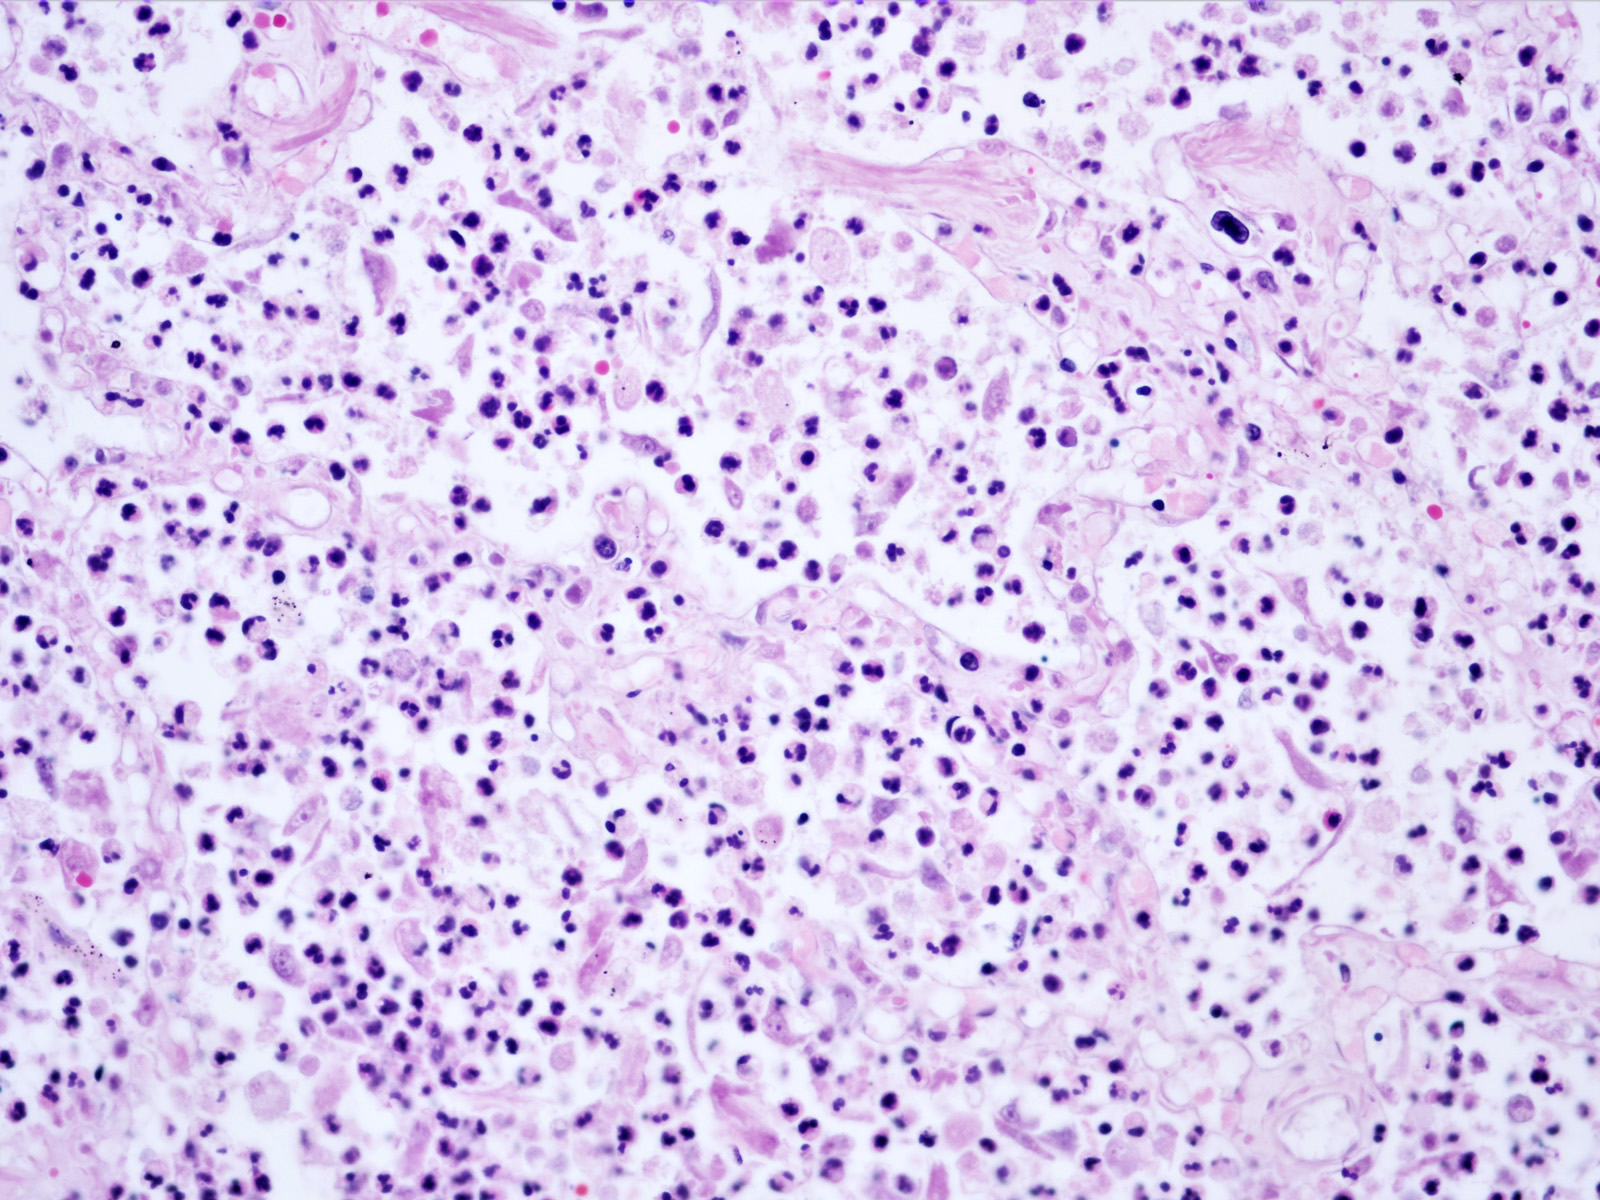

Microscopic (histologic) description

- Bronchopneumonia:

- Most common pattern of pulmonary infection

- Different stages in the different areas

- Patchy intra-alveolar fibrinopurulent exudate with neutrophils

- Acute lung injury pattern:

- Diffuse alveolar damage (DAD): hyaline membrane formation

- Organizing pneumonia (OP): fibrohistiocytic proliferation with obliteration of small airways (fibroblast plug, Masson body), accompanied by inflamed surrounding alveolar interstitium

Microscopic (histologic) images